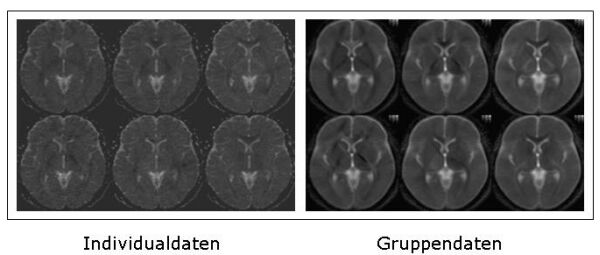

Abbildung 3: Durch die Mittelung der Daten mit korrekter Berücksichtigung der Richtungseigenschaften ist es möglich, den Rauschanteil zu vermindern und die Auflösung zu verbessern. Abbildung 3 zeigt einen Vergleich der Qualität der Diffusionsbilder zwischen Einzeldaten und Gruppendaten.

Abbildung 4: Darstellung von Individualdaten. Die Richtungsinformation der Hauptrichtung des Tensors kann mit sogenannten Richtungs-kodierten-Karten dargestellt werden. Hierbei werden Bildelemente, die Fasern enthalten, die von links nach rechts laufen in rot, Fasern von vorne nach hinten in grün und Fasern von oben nach unten in blau eingefärbt dargestellt. Die Bilder von Einzelprobanden zeigen auch Störungen durch messbedingtes Rauschen und geringe Auflösung.

Darstellung von Gruppendaten. Hingegen zeigen gruppengemittelte Bilder eine deutliche Verbesserung der Auflösung. Dies wird durch die Verwendung von Information aus mehreren Bildern ermöglicht. Daten in der ursprünglich geringen Auflösung werden an jeweils leicht verschiedenen Positionen aufgenommen. Durch Mittelung wird der Informationsgehalt erhöht, was eine verbesserte Auflösung ergibt. Verschiedene Faserbündel können klar unterschieden werden.